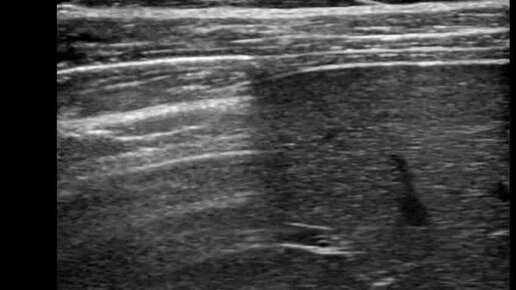

Ультразвуковые находки от врача УЗД Зорина Я.П.